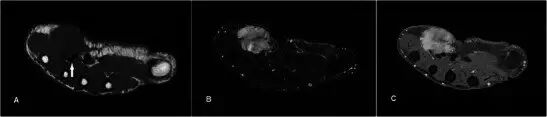

图1.24岁的女性腱鞘囊肿,呈现一个缓慢成长,坚定,无痛的手肿大约6个月。 (a)T1w序列显示在均匀低信号的大鱼际肌组织内的平滑、良好边缘病变。 (b)T2w-FS序列上的病变是高信号的。 没有看到侵入相邻结构。 (c)有最小的边缘增强,没有显着的内部增强(箭头)